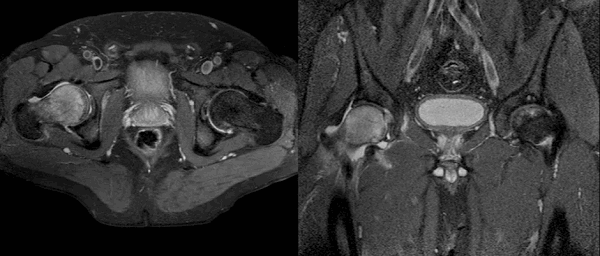

Рисунки 1,2. МР-картина артроза тазобедренных суставов с наличием отека костного мозга дистрофического характера в верхне-наружных отделах вертлужной впадины справа

Рисунок 3. МРТ тазобедренных суставов в косо-аксиальной плоскости.

Суставной хрящ головки бедренной кости и правой вертлужной впадины с обеих сторон однородной структуры, неравномерной толщины, целость его не нарушена. Головка бедренной кости сферичная, шейка не укорочена, не утолщена.